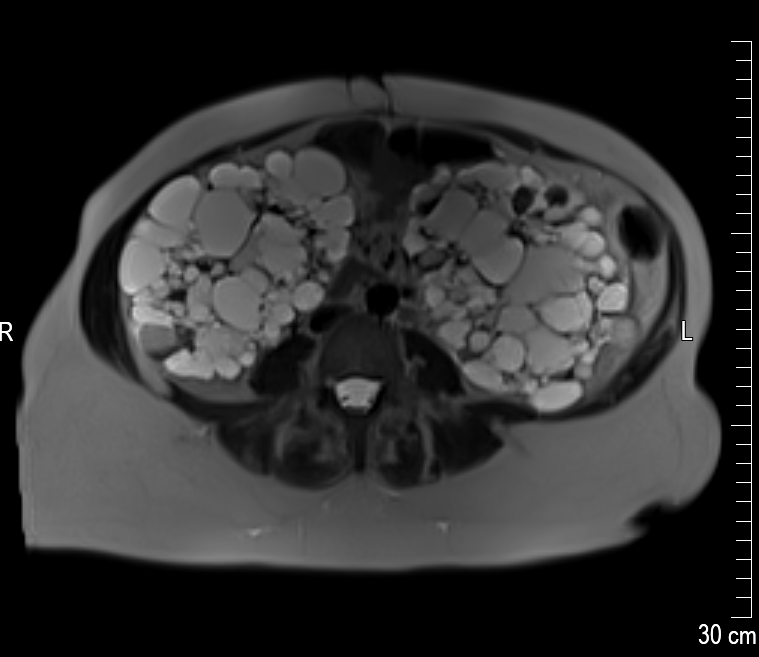

Die linke Niere ist circa 25 cm lang. Der große weiße Fleck unten ist eine der größten Zysten mit einer Länge von circa 8 cm. Die Niere ist so voluminös, dass sie eine richtige Beule ausformt. Die ist tatsächlich an meinem Körper sicht- und spürbar! In der rechten Niere befinden sich kleinere Zysten, dafür – so sieht es auf dem Bild aus – viel mehr als in der linken Niere. Alle anderen inneren Organe müssen den Nieren weichen – was mittlerweile zu starken Magenproblemen und teilweise auch Atemnot führt.

Es führt kein Weg mehr daran vorbei: Ich muss die linke Niere operativ entfernen lassen. Um Platz zu machen für ein mögliches Spenderorgan. Und um meinen Körper allgemein etwas zu entlasten.